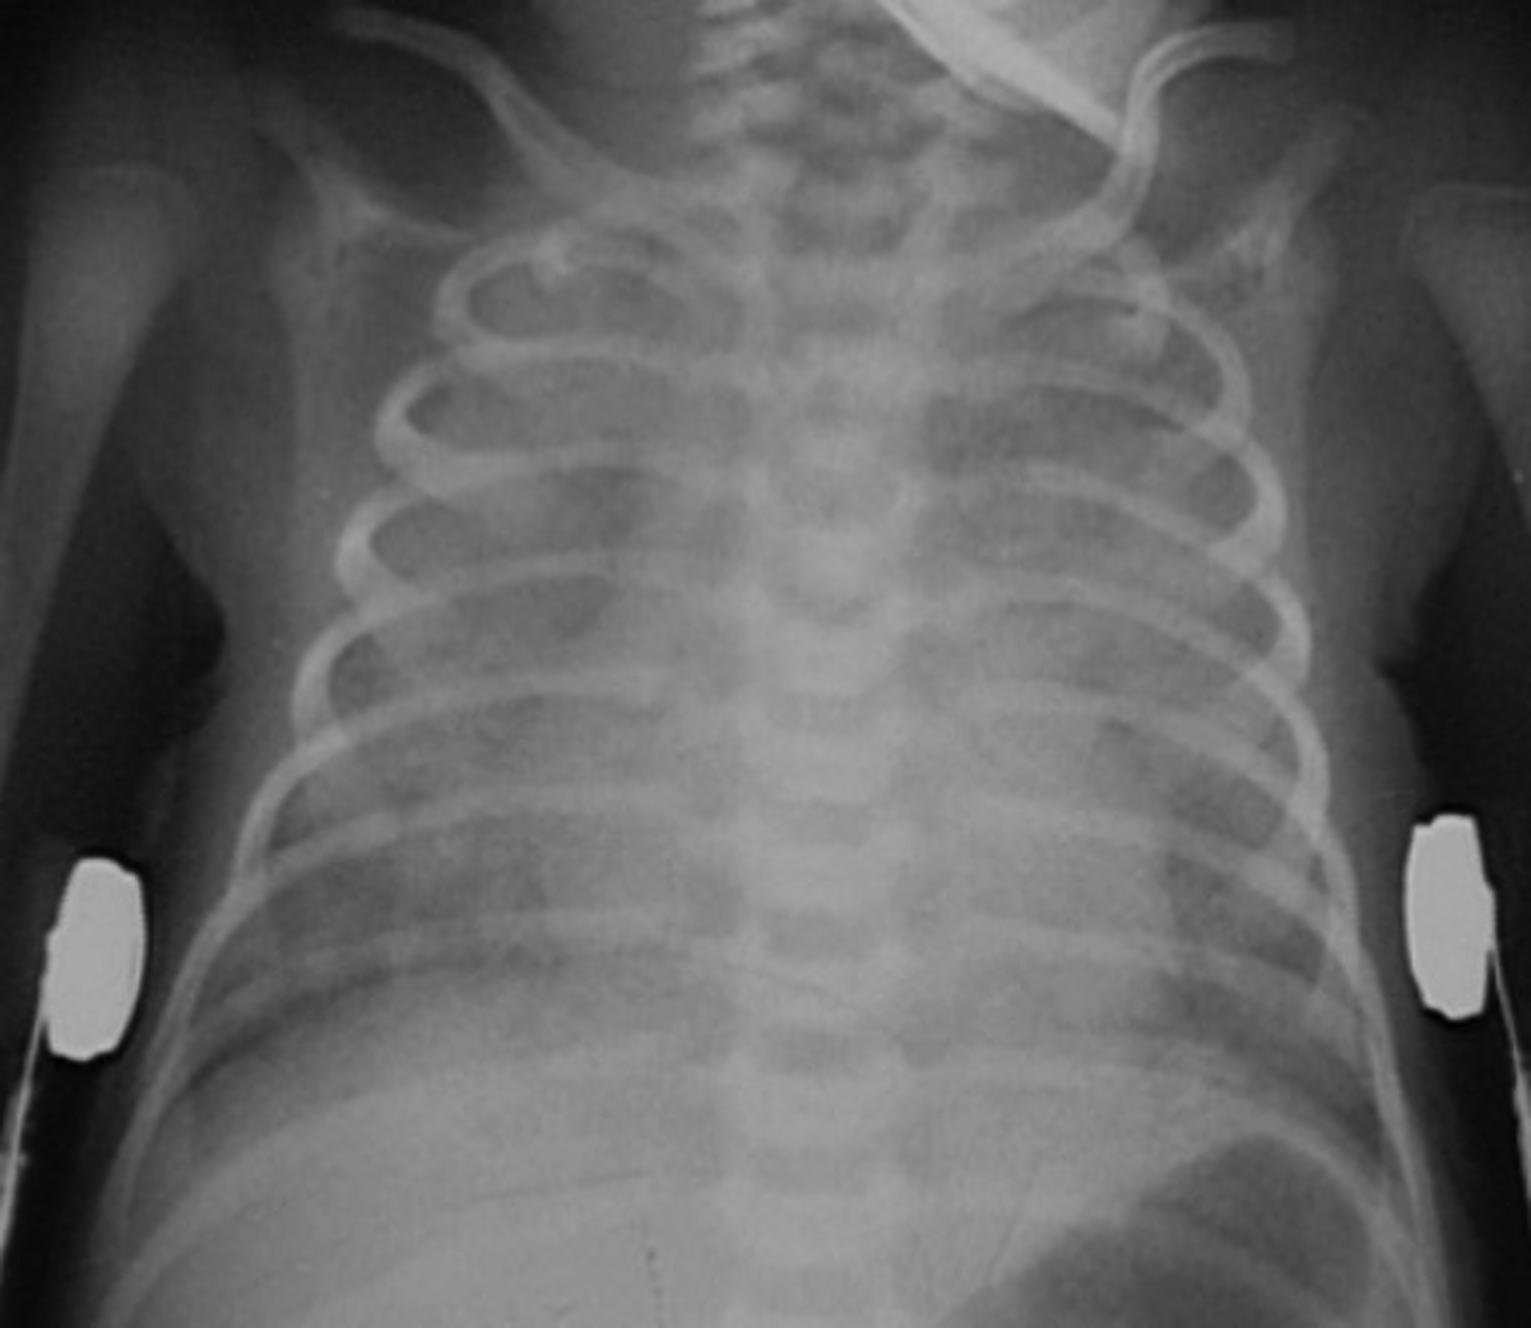

A 7-day-old female patient is brought to your emergency department by ambulance for difficulty breathing. She was born via spontaneous vaginal delivery at 37 weeks gestation and had an uncomplicated hospital stay and was discharged at the end of day 2 post-delivery. Over the past day she began developing a cough and fever to 101°F, decreased feeding, and “fast breathing”. Her vital signs are significant for a heart rate of 180 beats per minute, a rectal temperature of 102.1°F, a blood pressure of 78/44mmHg, a respiratory rate of 70 breaths per minute, and an oxygen saturation of 85% on room air. On physical examination she appears lethargic. She is tachypneic with retractions bilaterally, slightly dry mucous membranes, and coarse breath sounds over the right lower lobe. Despite supplemental oxygen via nasal cannula at 6 liters per minute, her oxygen saturation only increases to 91%. Her chest radiograph (CXR) is seen in Figure 2.1.

FIGURE 2.1. AP view of the chest demonstrates bilateral diffuse pulmonary air space opacification.